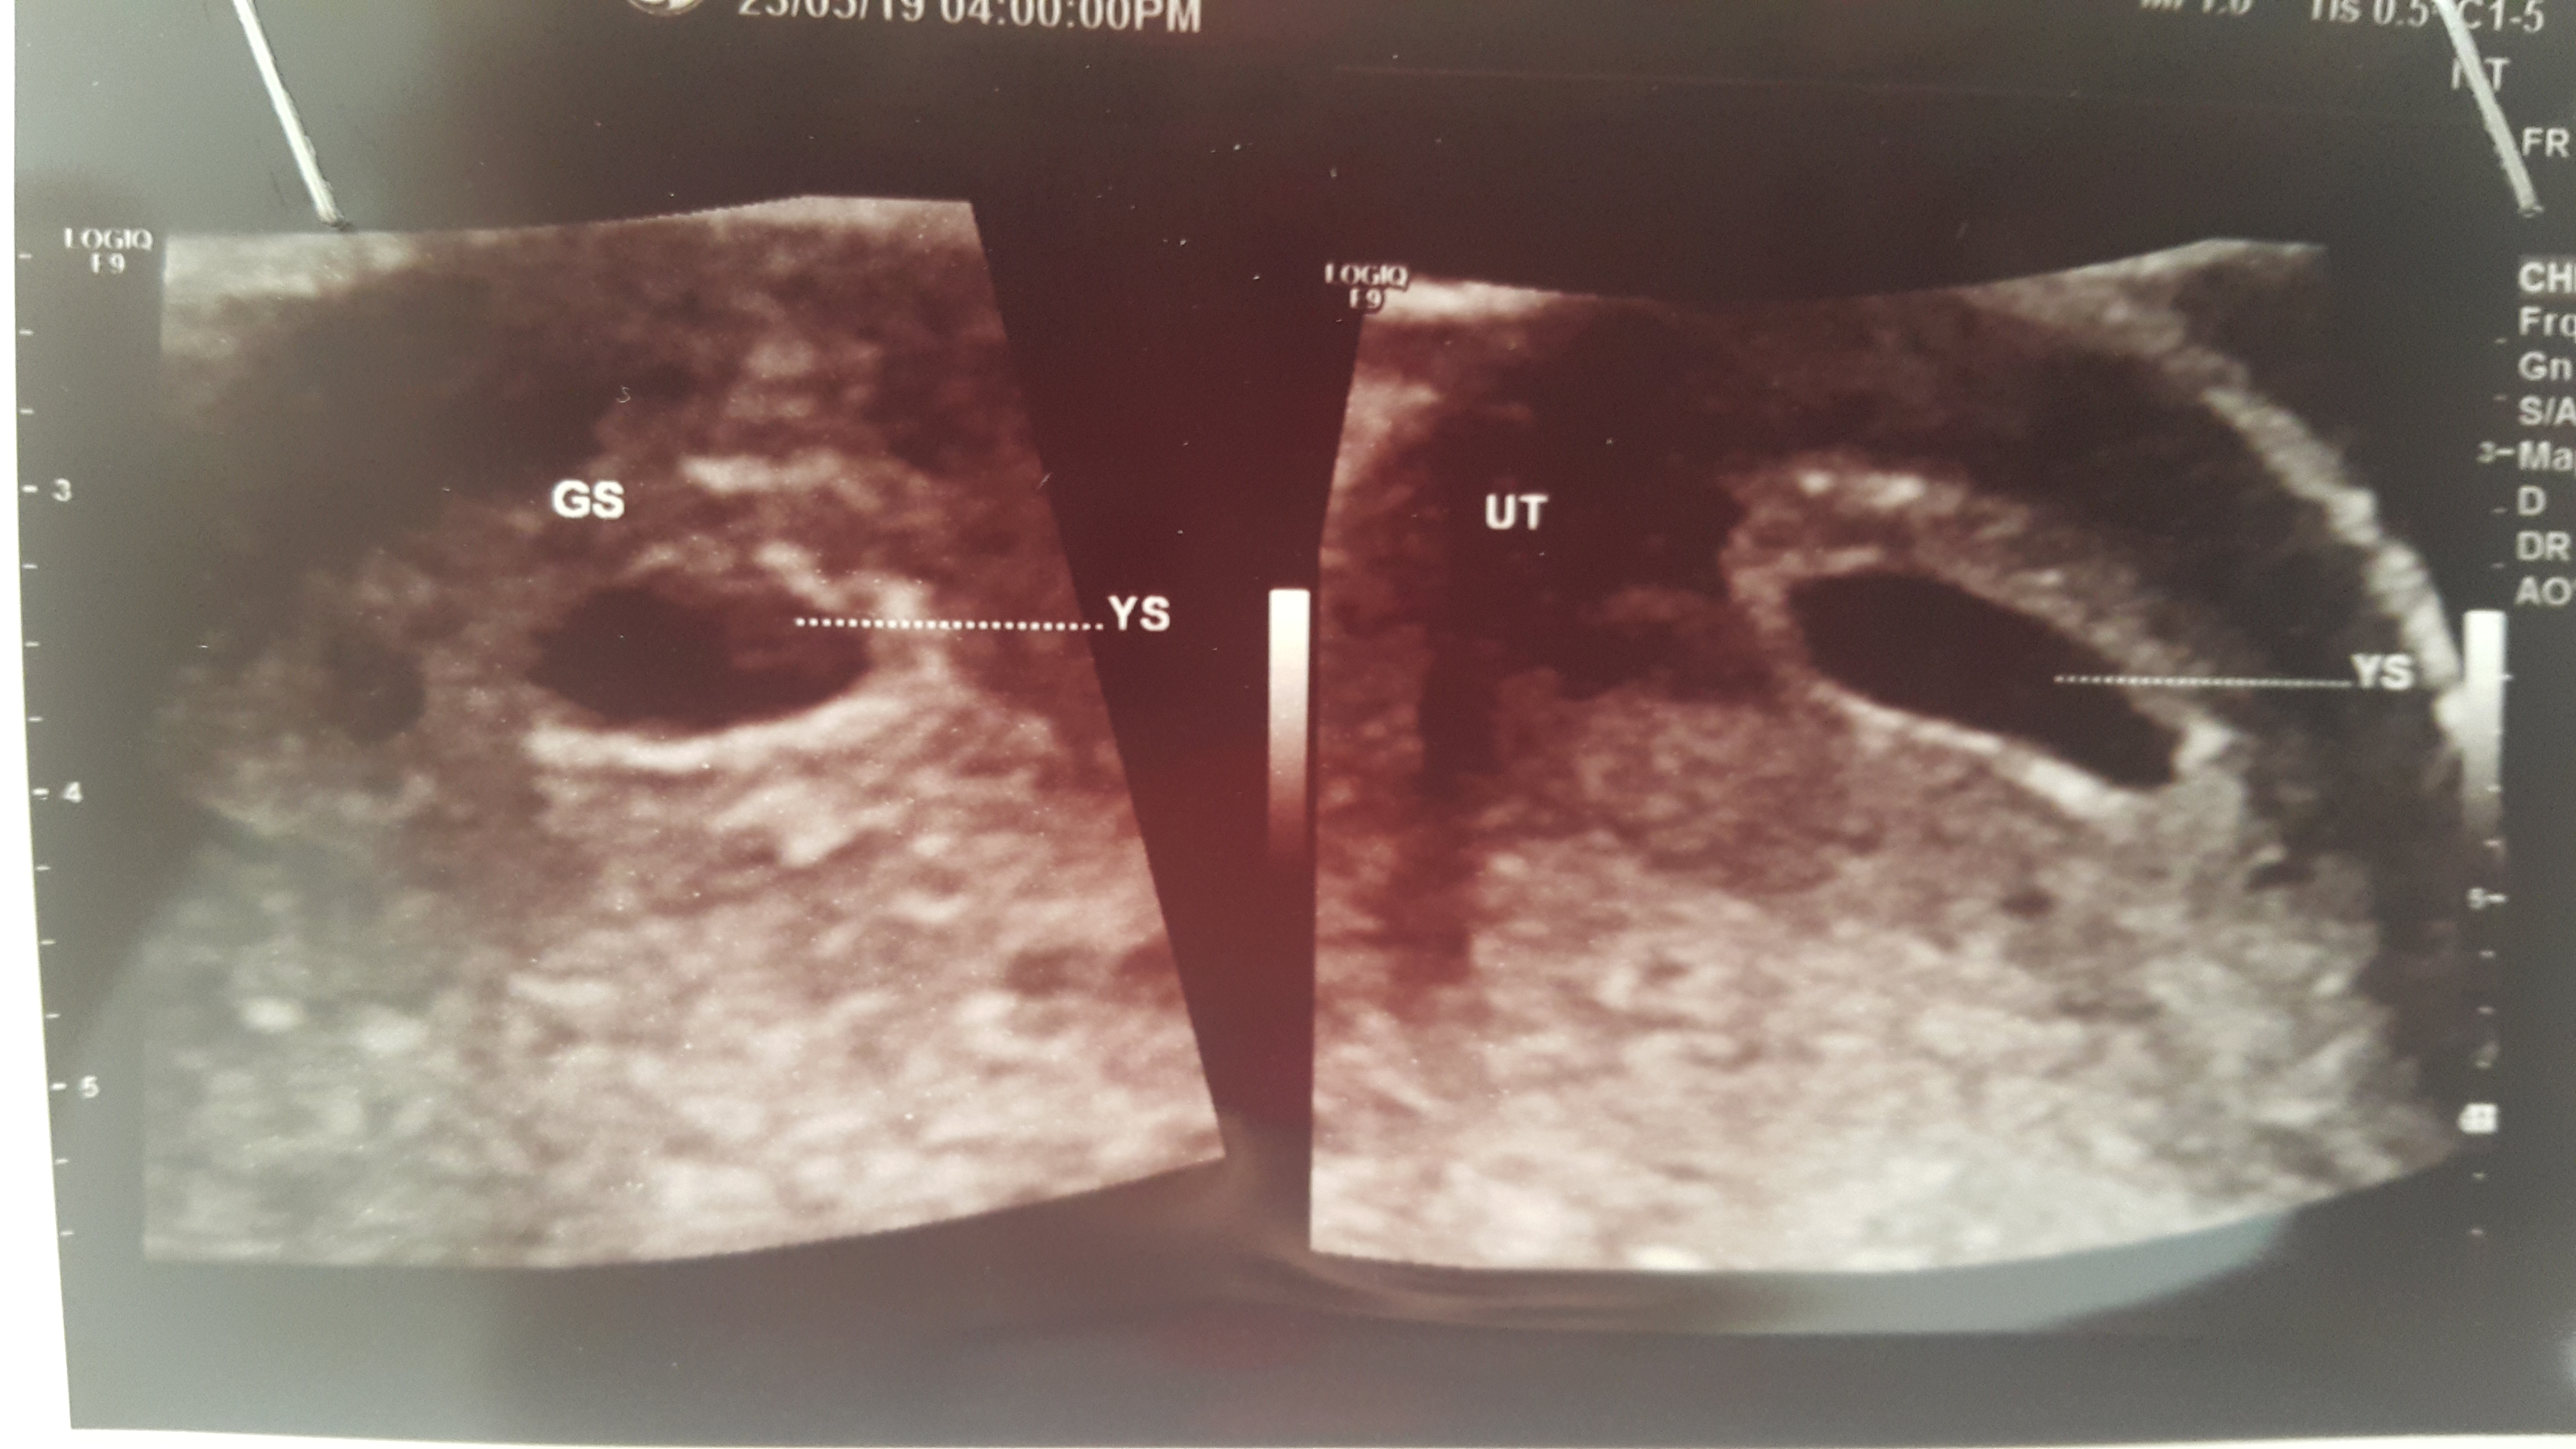

من_نه_منم_نه_من_منم عضویت: 1397/02/16 تعداد پست: 1988 زده که کیسه زرده دیده شد که y.sیعنی کیسه زرده دیگه مخفف دختر قشنگم دنیز خانم ۹۸/۱۰/۱۰ ساعت ۱۰:۱۰ امد بغل مامانش قربونت برم دختر نازم

askim_nazam مدیر استارتر عضویت: 1397/11/30 تعداد پست: 3964 زود رفتی کیسه زرده دیده نشده منم زود رفتم نبود باز سونو نوشته برام نوشتهy.sبا جدار منظم من دلم به اون خوش بود فک میکردم کیسه زرده هستش اون آخه ی نقطه ای تو کیسه آب بود توی مانیتور معلوم بود عکسشو ببین اون چیه علامت زده؟زود رفتم ۶هفته بودم ک اینجا گفت ۵هفته ونیم هستی 👪

مامان_باران_ترنم عضویت: 1398/02/18 تعداد پست: 937 عزیزم نوشته ساک حاملگی تشکیل شده و توش جنین هست ولی قلبش هنوز تشکیل نشده.... 5هفتع و 5 روز هستی.... زود رفتی..... هفته 8 به بعد برای تشکیل قلب باید بری

askim_nazam مدیر استارتر عضویت: 1397/11/30 تعداد پست: 3964 فك كنم نوشته ساك حاملگي هست اما جنين نديده زور رفتي؟! بعدم فك كنم نوشته كيست ديده آره زود رفتم ۶هفته و۲روز بودم ک به حساب سونو گفت۵هفته ونیممآره ی کیست تو تخمدان چپم دارم یکمم مایع آزاد تو لگنم دیده شد 👪